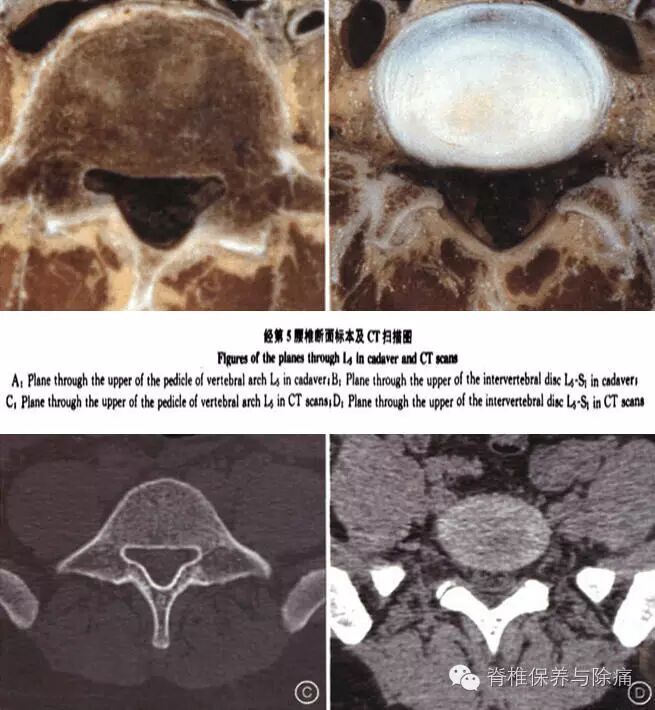

侧隐窝,即脊神经管。脊柱椎管分中央椎管和侧隐窝,侧隐窝又称为神经根管,是椎管两侧的延伸,是骨性椎管最狭小的部分,内有脊神经根通过。为椎管的外侧部,其前部为椎体后外侧缘,后壁为上关节突前面与黄韧带,外界为椎弓根。其矢径越小,横径越大,表示侧隐窝越窄越深。脊椎解剖学特点是L3~S1椎管逐渐变大,其相应的椎管侧隐窝也大,而S1以下椎管自上而下逐渐变小。侧隐窝主要由椎弓根与椎体的后缘所构成,它的外侧壁为椎弓根的内方,前壁为椎体和椎间盘的后缘,后壁是上关节突和部分黄韧带,其中构成侧隐窝的任何一个因素发生变化,均可导致侧隐窝的狭窄,尤其是骨性的狭窄。

在腰段,腰椎管的两侧部分对椎间盘者称盘黄间隙,平对椎体者称侧隐窝。侧隐窝向下续于椎间孔,腰部较狭窄。第5腰椎椎管呈三叶形者,侧隐窝尤为明显,侧隐窝的前后径通常为3~5mm;若小于3mm,则可认为侧隐窝狭窄;若大于5mm,则肯定不狭窄。盘黄间隙可因椎间盘后突、黄韧带肥厚或关节突增生内聚而缩窄,这时受压迫的是下一位,甚至是下两位的脊神经根。只有在L4~5和L5~S1盘黄间隙才能同时压迫下位神经根硬膜囊外段。由于同序数的神经根并未进入盘黄间隙即转向外出椎间孔,故不受影响,椎间盘突出压迫神经根以L4~5和L5~S1,盘黄间隙处为常见,其压迫方向有从神经根内、外侧或前方向后顶三种,但以后者多见。侧隐窝狭窄,容易产生神经刺激症状。多见于腰椎。产生刺激的来源多是增厚的黄韧带、突出的椎间盘、此处的骨赘(俗称骨刺)